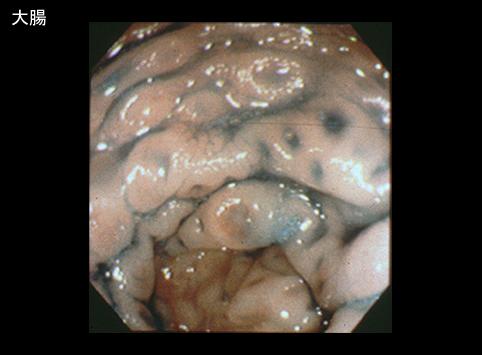

疾患(病理主体)の分類悪性リンパ系腫瘍/MLP型悪性リンパ腫

部位(臓器別)大腸/その他

検査方法内視鏡

病変の最大径(ミリ)1〜9

多発腫瘍(同一臓器)有(同・異時性)

多重腫瘍(他臓器)有(同・異時性)